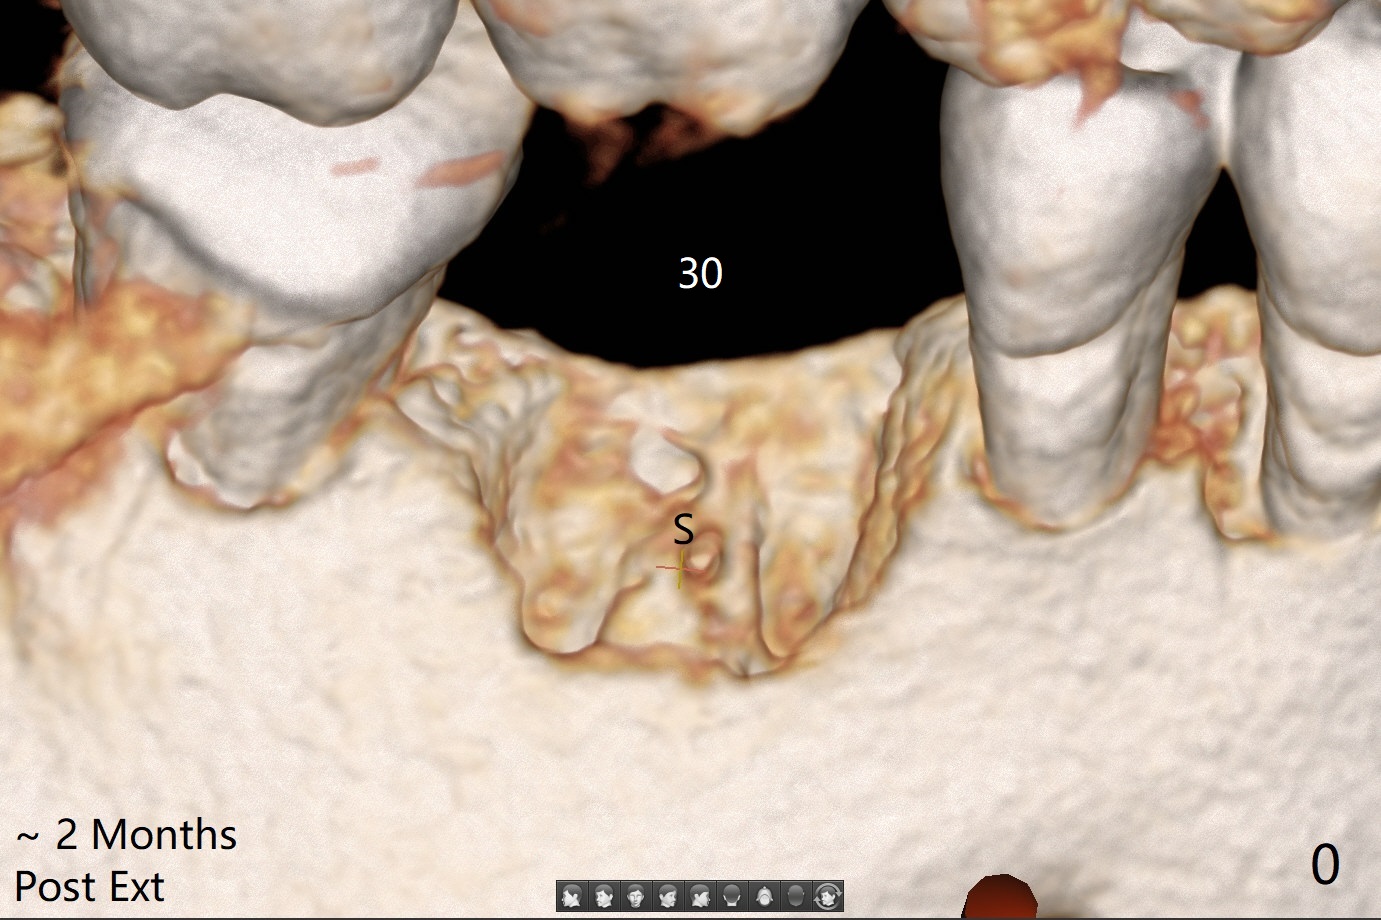

The sockets of #30 (M) of a smoker (M) are apparently not healing ~ 2 months post extraction (Fig.0, 0'). The ridge looks wide 3 months post extraction without bone graft in other office before (Fig.1) and after (Fig.2) flap surgery. The socket appears to have healed perfectly consi-dering buccal defect (M) revealed by CT ~ 1 month earlier. When a 5x10 mm implant is placed with guide and high torque (in spite of overprep), granu-lation tissue is found mesio-buccal (MB, Fig.2 *). After curettage, bone graft is placed around the implant, especially MB (Fig.3 *), followed by PRF. Periodontal dressing dislodged a few days postop because of mastication on the right side (Fig.4), whereas the anterior one (24/26) remains in place. There is a small gap around the implant when it is uncovered (Fig.5 arrowheads). It appears that some of bone graft gets lost from the incision (smoker). A 6.5x5.5(4) mm cemented abutment is seated and torqued at 30 Ncm before impression (Fig.6). There is no bone loss 11 months post cementation (Fig.7).